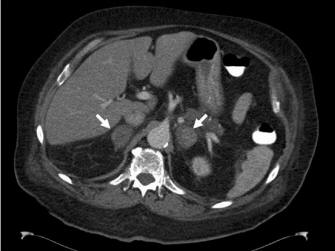

ADRENAL HEMORRHAGE MIMICKING AN ABDOMINAL AORTIC ANEURYSM

Symptomatic adrenal lesions tend to be larger and commonly present in younger patients. Adrenal metastases most commonly originate from a primary lung tumor, followed by stomach, ... Return Doc